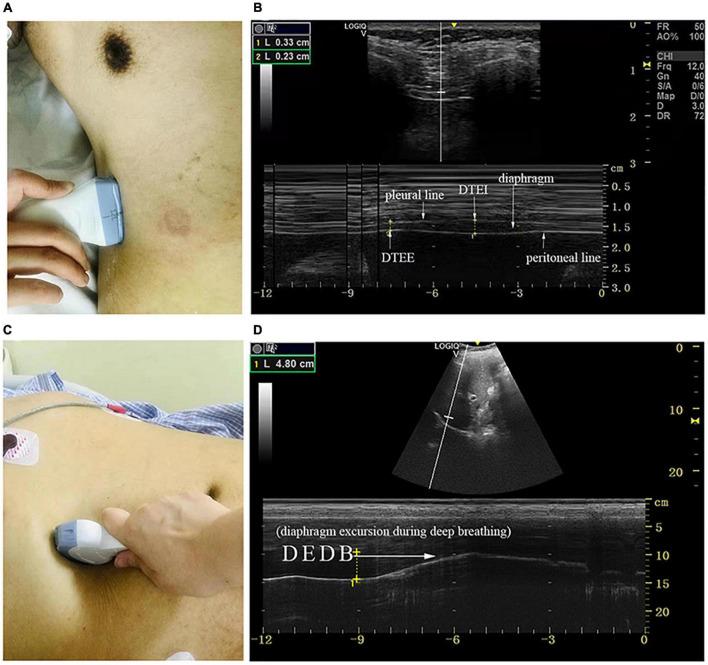

In normal subjects, the diaphragm plays a key functional role in postural stability, articulation, respiration, defecation, and urination. The aim of this study was to investigate the role of the diaphragm in postural stability and visceral function in patients with Parkinson's disease (PD) and to compare the diaphragm function by gender, Hoehn and Yahr (H&Y) staging, and motor subtypes. In total, 79 patients were enrolled in this cross-sectional study. The severity of the disease was assessed by the Movement Disorder Society-Unified Parkinson's Disease Rating Scale III and by H&Y staging. Postural stability was quantitatively recorded, and respiratory function was evaluated by spirometry. Several scales were used to evaluate visceral function in patients with PD. In addition, diaphragm ultrasound was used to measure the excursion, contraction velocity, and thickness of the diaphragm during quiet breathing, deep breathing, and the sniff test. Significant features were selected by the least absolute shrinkage and selection operator (LASSO) regression and fitted in the multivariate linear regression and Pearson's correlation analysis. Diaphragm thickness and excursion during quiet breathing were significantly different between men and women and between H&Y stage 1-2 and stage 2.5-3, whereas the diaphragm function was not influenced by motor subtypes. It was shown that the diaphragmatic function was significantly correlated with postural stability, voice function, respiratory function, constipation, and urological function to varying degrees in patients with PD. The diaphragmatic function is associated with dysfunction in PD although it remains unclear as to whether the observed changes in the diaphragm are primary or secondary.

在正常受试者中,膈肌在姿势稳定性、发音、呼吸、排便和排尿中发挥关键的功能作用。本研究的目的是调查膈肌在帕金森病(PD)患者姿势稳定性和内脏功能中的作用,并按性别、霍恩和雅尔(H&Y)分期以及运动亚型比较膈肌功能。共有79例患者纳入了这项横断面研究。通过运动障碍协会统一帕金森病评定量表III和H&Y分期评估疾病严重程度。定量记录姿势稳定性,通过肺活量测定评估呼吸功能。使用多个量表评估PD患者的内脏功能。此外,采用膈肌超声测量静息呼吸、深呼吸和嗅气试验时膈肌的移动度、收缩速度和厚度。通过最小绝对收缩和选择算子(LASSO)回归选择显著特征,并将其纳入多元线性回归和Pearson相关性分析。男性与女性之间以及H&Y 1-2期与2.5-3期之间静息呼吸时的膈肌厚度和移动度存在显著差异,而膈肌功能不受运动亚型的影响。结果表明,PD患者的膈肌功能与姿势稳定性、语音功能、呼吸功能、便秘和泌尿系统功能在不同程度上显著相关。膈肌功能与PD功能障碍相关,尽管尚不清楚观察到的膈肌变化是原发性的还是继发性的。